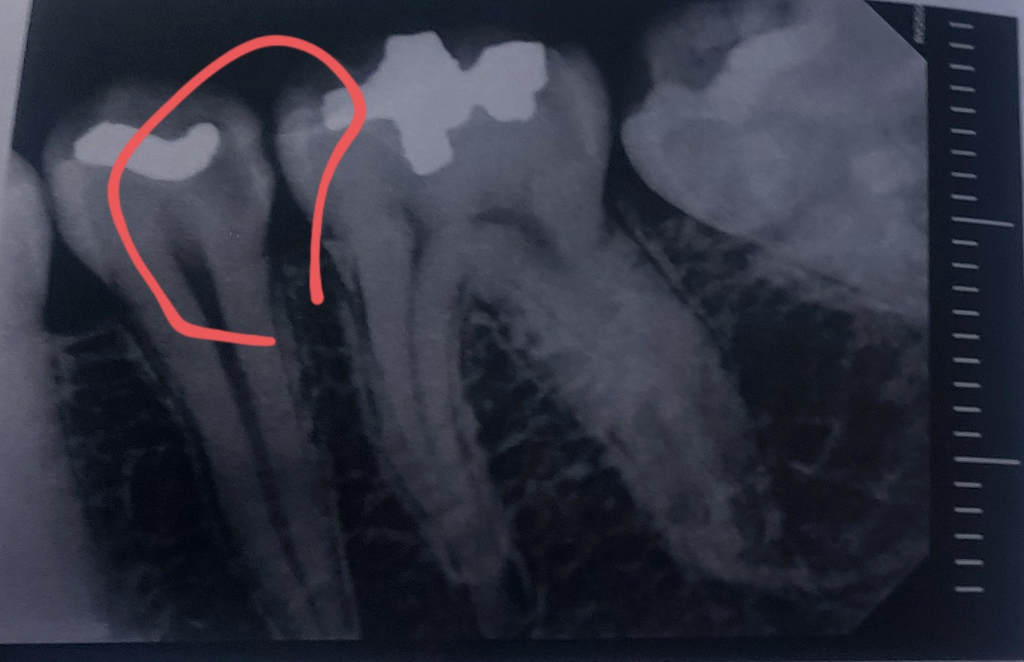

육안으로 보이는 충치는 없어서 바람 쏘면서 시린지 물어보셨고 시리지 않다고 하니 아이스막대로 확인해보셨습니다. 시린 증상 있는 이가 총 두 개 였구요 그 두 개만 집중적으로 사진 찍어서 보여주셨습니다

사진 보시자마자 두 개 다 신경치료해야한다고 하시던데 제가 일단 검진만 계획하고 와서 다음에 다시 오겠다하니

• 2번 째 사진

사진상으로는 신경치료를 해야될 가능성이 높습니다만

충치는 제거를 해봐야 확실히 알 수 있습니다

엑스레이 상으로 봐도 충치가 깊어 보입니다. 신경치료를 해야될 가능성이 높아 보이네요.